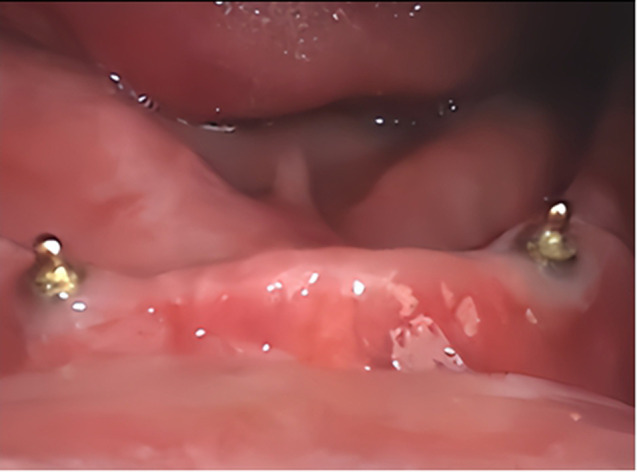

Methods: In this study, twenty-two male patients who were completely edentulous participated in a rehabilitation program involving mandibular overdentures retained by two dental implants placed in the canine area. The subjects were categorized into two equal groups, each comprising eleven patients. Group I received mandibular overdentures fabricated from conventional acrylic denture bases, whereas Group II received mandibular overdentures with bases that had undergone nanogold treatment. Microbial growth and colonization were evaluated around the implant's necks and the fitting surface of each patient's mandibular dentures. Three types of bacteria were studied: Candida albicans, Escherichia coli, and Streptococcus mutans. The mean difference in the counts of bacteria before the denture was inserted and after two, four, and six months has been calculated and analyzed statistically.